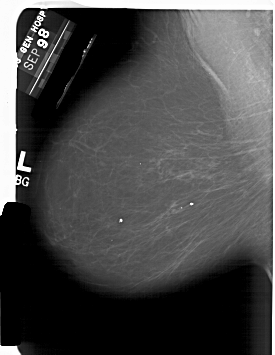

A_1850_1.LEFT_CC

LEFT_MLO LINES 6376 PIXELS_PER_LINE 4936 BITS_PER_PIXEL 12 RESOLUTION 43.5 NON_OVERLAY